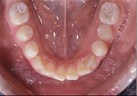

Right Buccal View Frontal View Left Buccal View Maxillary View Mandibular View

Dental Casts

right buccal frontal left buccal upper mandibular